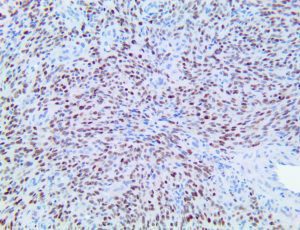

The first cytokines released are interleukin 1β (IL-1β) and tumor necrosis factor-α (TNF-α), which attract a variety of circulating white blood cells (WBCs) to the infection site, including neutrophils, monocytes, macrophages, and natural killer (NK) cells. This response, along with the antipathogenic chemicals released by these cells (i.e., complement), comprise the innate immune response. These cells directly attack the invading pathogen and also release additional cytokines, chief among them interleukin-1 and 6 (IL-6). IL-6 is essential for invoking the adaptive immune response, which calls T-cells, B-cells, and T helper (Th) cells to the infection site. IL-6 also stimulates further recruitment, proliferation and activation of macrophages.

It is the ICU physician who is most likely to witness one of the deadliest manifestations of the abnormal immunological response, the cytokine storm syndrome (CSS). This response is also referred to by some as the cytokine release syndrome (CRS). CSS is characterized by continuous activation and expansion of macrophage and lymphocyte populations, which secrete large amounts of cytokines, causing the cytokine storm. This massive cytokine release is akin to hemophagocytic lymphohistiocytosis (HLH) disease, a syndrome characterized by initial unchecked and persistent activation of cytotoxic T lymphocytes and NK cells.